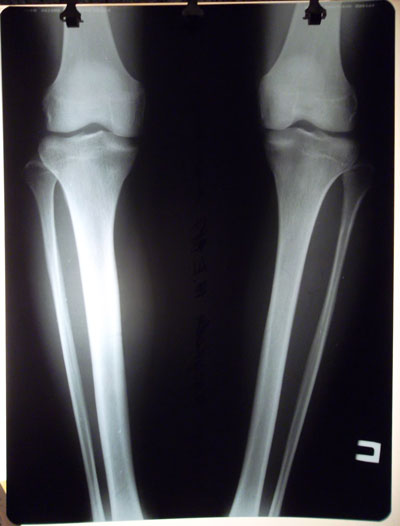

Дорбый вечер, разместите, пожалуйста, ренген-снимки до операции. Хотелось бы сравнить. Заранее спасибо

Здравствуйте, Жанна! По Вашей просьбе, рентген голеней в прямой проекции до операции разместила.

SAM_9319.JPG